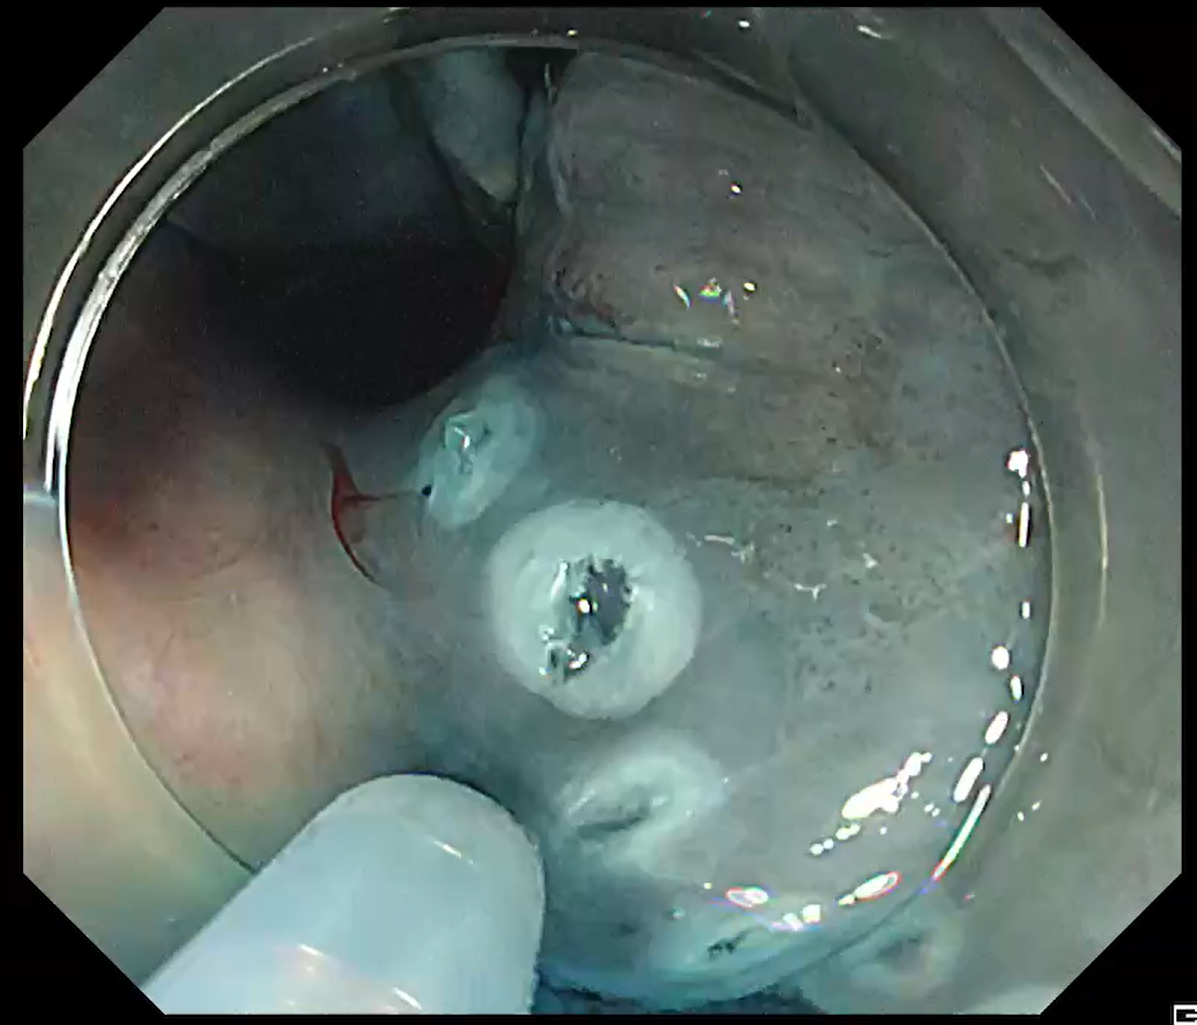

A 50 mm laterally spreading tumour in the ascending colon was addressed (Fig. 13). With ITknife nano the fundamental manoeuvre is “inside to outside”, advancing toward the lumen (Fig. 14).

Even when a large vessel or ambiguous fold obscured the plane, safe dissection was possible by first creating a small ‘hold’ on the vessel side – lightly melting the blue submucosa with the insulated tip – then continuing the inside to outside approach (Fig. 15, Movie 3).

Should gravity or scope instability slow progress, traction is applied to stand up the submucosa. Once the tissue is standing, rapid dissection can be performed with the ITknife nano without altering patient position, completing the resection efficiently.